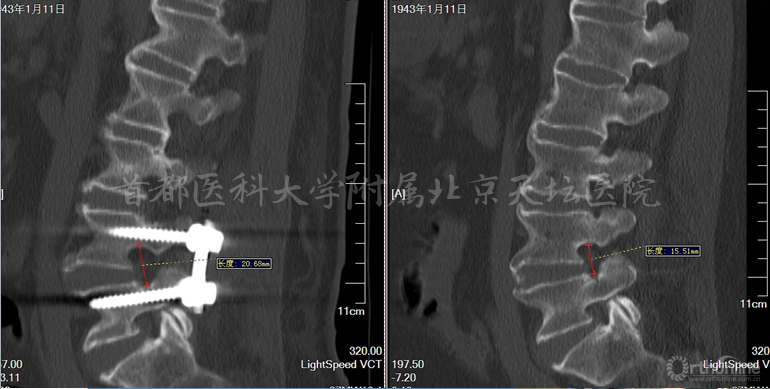

影像资料:

针对此病例,各位专家的讨论焦点主要落在棘突间植入物的疗效究竟如何上。天坛医院刘宝戈教授针对这个病例指出,患者曾在外院行棘突间植入物手术,术后不久再次出现症状,翻修手术如何进行?这需要细致的考量。针对该例老年患者,他们最终选择了微创的治疗方式,基于术前精确责任节段的定位,术后疗效满意。